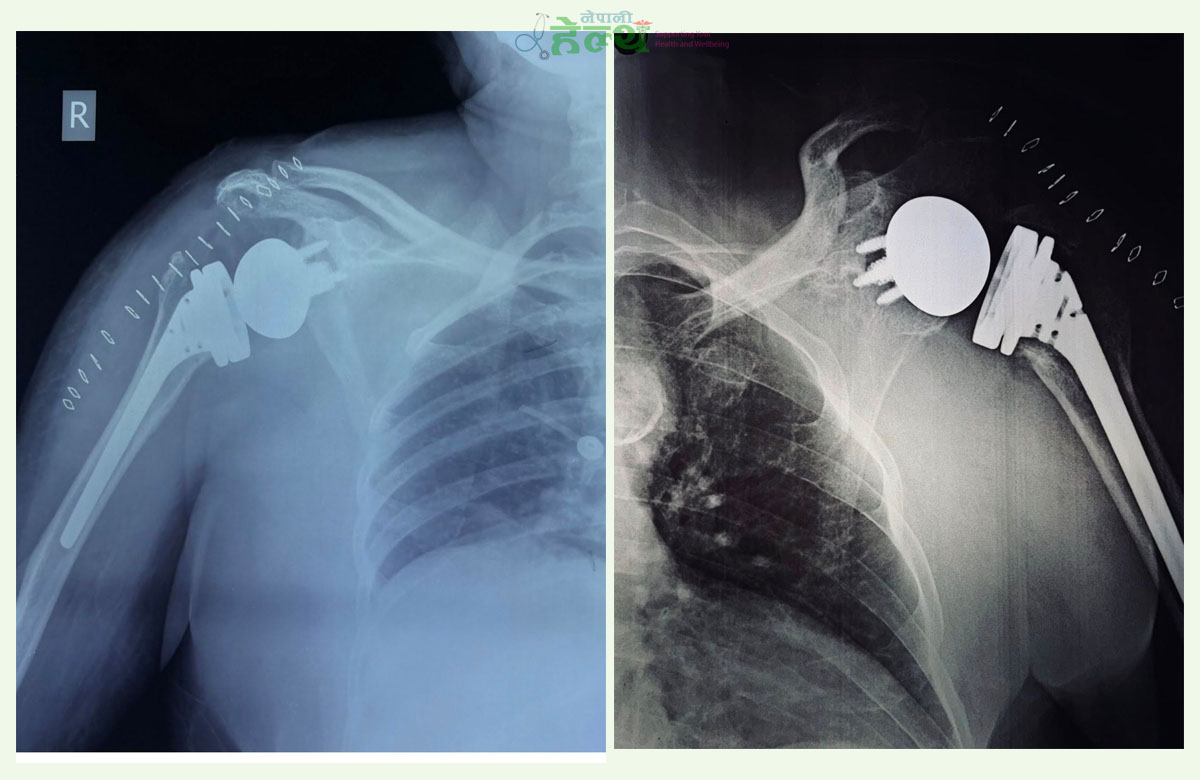

डा. थापा भन्छन्, ‘काँधको जोर्नी प्रत्यारोपण दुई प्रकारका हुन्छन्—‘टोटल शोल्डर रिप्लेसमेन्ट’ र ‘रिभर्स शोल्डर रिप्लेसमेन्ट’। रिभर्स प्रविधिमा भने जोर्नीको संरचना नै उल्ट्याइन्छ। उनका अनुसार सामान्य अवस्थामा गेडी कपमा घुम्ने भए पनि रिभर्समा कपलाई गेडी र गेडीलाई कप बनाइन्छ।

सामान्य रूपमा काँधको जोर्नी ‘बल एन्ड सकेट’ प्रणालीमा आधारित हुन्छ। माथिल्लो हातको हड्डी ह्युमेरसमा गेडी ९बल० हुन्छ भने स्कापुलाको ग्लेनोइड भागमा कप (सकेट) हुन्छ। यही गेडी कपभित्र घुमेर हात चल्ने गर्छ।

यस प्रक्रियामा ग्लेनोइड भागमा धातुको गेडी (ग्लेनोस्फियर) राखिन्छ भने ह्युमेरसमा प्लास्टिकको कप जडान गरिन्छ। यसरी संरचना उल्ट्याउँदा बिग्रिएको रोटेटर कफ मांसपेशीको सट्टा डेल्टोइड मांसपेशीले काँध चलाउने मुख्य काम गर्छ।